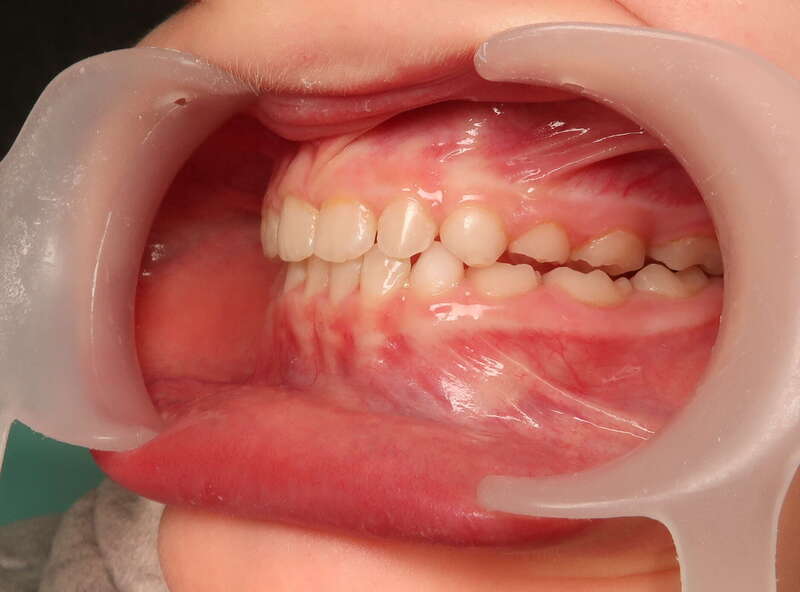

Cas n°1 d'orthodontie chirurgicale par aligneurs - adulte

Voici l'analyse de ce cas clinique concernant un patient adulte de 30 ans, illustrant la réussite d'un protocole ortho-chirurgical mené avec des aligneurs. Ce cas met en lumière l'importance de la fonction musculaire et respiratoire au-delà de l'alignement dentaire.

À 30 ans, la croissance est terminée, ce qui rend la correction d'un décalage osseux uniquement possible par la chirurgie :

• Rétrognathie Mandibulaire (Profil Rétrusif) : Le patient présentait un menton fuyant, caractéristique d'une mandibule trop courte ou positionnée trop en arrière.

• Déficit Fonctionnel : L'absence d'engrènement correct entraînait une mastication inefficace. Le patient rapportait une sensation de "manque de force" lors de l'alimentation.

• Supraclusion et Décalage : Un recouvrement incisif important qui bloquait toute dynamique mandibulaire saine.

• Usure et Fatigue : Chez l'adulte, ces malpositions entraînent souvent des tensions musculaires et une usure prématurée du capital dentaire.Le traitement a combiné la précision numérique des aligneurs et la puissance de la chirurgie maxillo-faciale :

1. Préparation par Aligneurs : Les arcades ont été préparées (alignement et coordination) pour que, une fois la mâchoire avancée par le chirurgien, les dents s'emboîtent immédiatement.

2. Avancée Mandibulaire Chirurgicale : Le repositionnement osseux a permis de corriger le profil de manière spectaculaire, redonnant de la force et de la structure au bas du visage.

3. Réhabilitation de la Force Masticatrice : C'est le point clé du ressenti patient. En retrouvant un engrènement de Classe I, les muscles masticateurs travaillent enfin avec un rendement optimal. Le patient ressent physiquement ce retour de puissance musculaire.

4. Harmonie du Profil : L'avancée du menton a équilibré les proportions du visage, offrant un profil plus affirmé et une meilleure définition de la ligne mandibulaire.